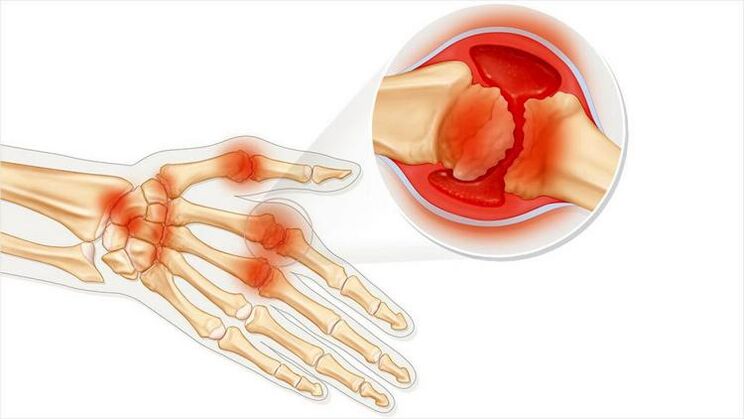

Arthrosis is a common disease caused by problems in the cartilage.They begin to gradually disintegrate and break down, leading to unbearable pain.Occurs in both acute and long -term forms.Often appears in the morning or after a severe physical activity.

Common arthritis is a state of joint inflammation.Mainly expressed as swelling and redness.The inner lining of the knot is destroyed, resulting in pain that is often difficult to simply endure.

Both diseases have a common root in their names "Arthron".If you translate it from Greek, you get "common".Both diseases are associated with joint problems and pain.Such pathologies occur with acute negative sensations and discomfort.Lesions associated with the border of the cartilaginous layer and intricate movement.